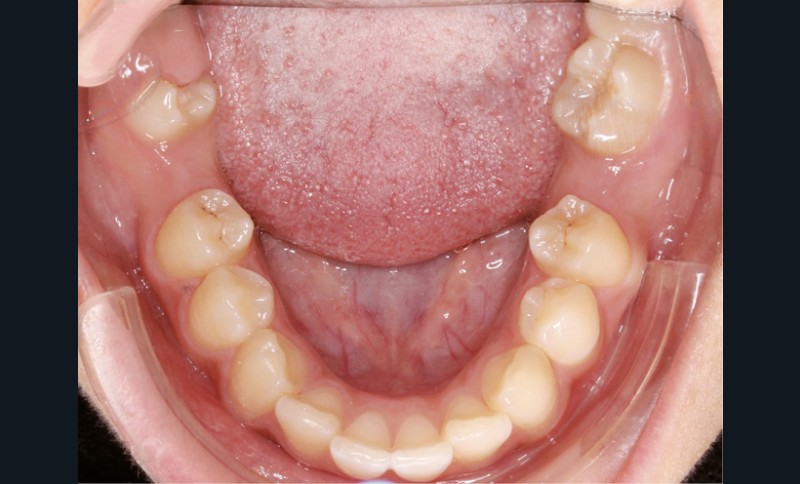

Examen endobuccal (fig. 2a-e)

L’hygiène est satisfaisante et le parodonte sain. On note aux deux arcades l’absence des premières molaires et la fermeture partielle des espaces d’extraction avec mésiorotation marquée de 17, 27 et 37. À la mandibule, l’encombrement antérieur est estimé à 2 mm et les espaces d’extraction résiduels à 12 mm.

Dans le sens transversal, malgré une occlusion correcte des secteurs latéraux, on observe une endoalvéolie maxillaire et une non-concordance des médianes incisives avec déviation de la médiane mandibulaire vers la droite. Le recouvrement incisif est normal.